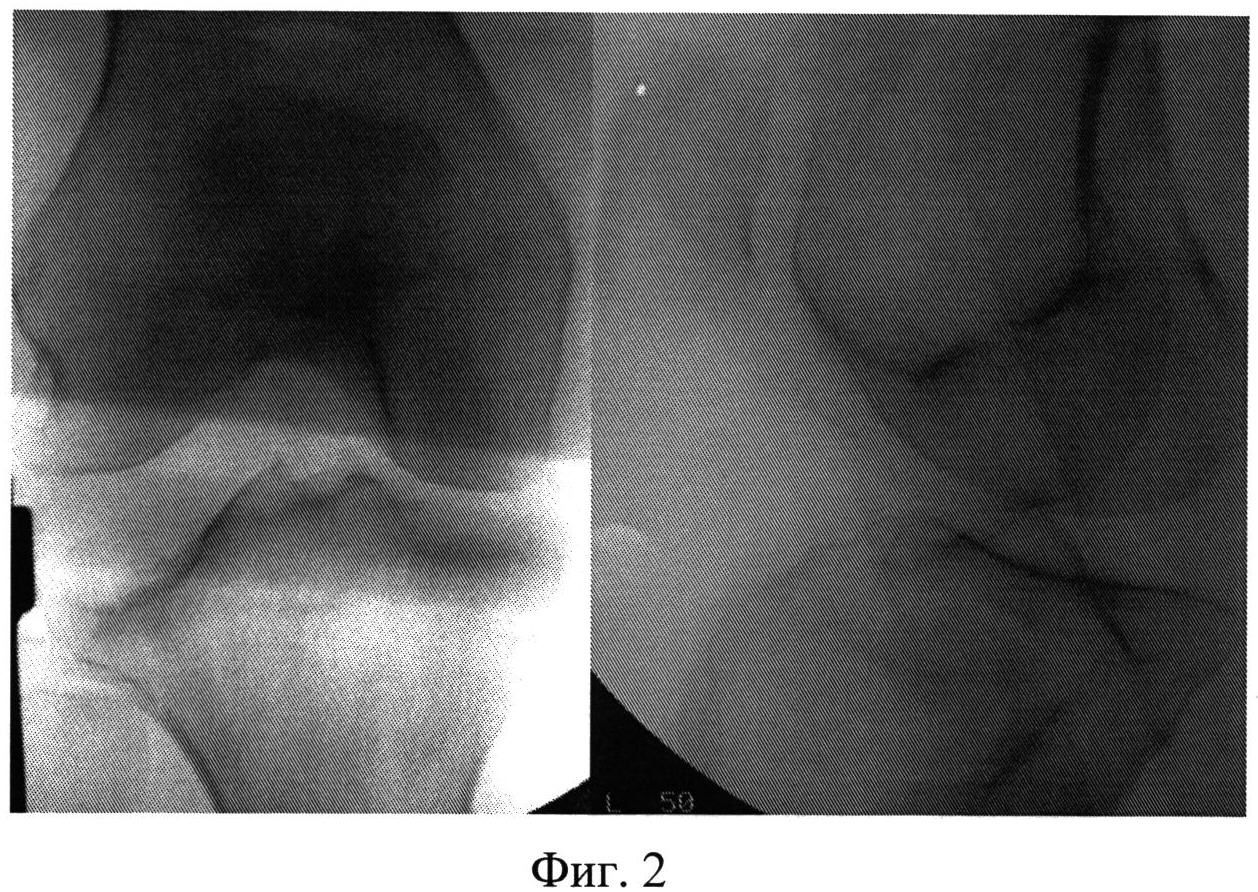

Фиг.2 - копии рентгенограмм правого коленного сустава в прямой и боковой проекциях.

Больная Д., 52 года. Травма получена 05.06.2013 в результате падения на улице с опорой на область левого коленного сустава. Госпитализирована в травматологическое отделение №1 МБУ ЦГКБ №24 с диагнозом: Импрессионный перелом наружного мыщелка левой большеберцовой кости (В2.3; Schatzker II) (Фиг.2).